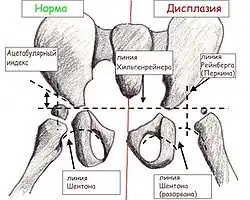

Большая часть головки бедра и вертлужной впадины у детей раннего возраста состоит из хрящей, которые невидимы на рентгеновском снимке, поэтому для чтения рентгенограмм применяют различные схемы.

Прежде всего проводят вертикальную срединную линию, она проходит через середину крестца. Проводят горизонтальную линию через У-образные хрящи, через нижние точки подвздошной кости (линия Хильгенрейнера). Через наружно верхний край, перпендикулярно горизонтальной линии проводят линию Перкина. Часто бывает, что на стороне поражения невозможно определить верхний край вертлужной впадины. В этих случаях пользуются методом Рейнберга: симметрично, на таком же расстоянии от срединной линии проводят вертикальную линию (перпендикулярно горизонтальной). Она и будет обозначать невидимый на рентгенограмме верхнелатеральный край впадины. Через края вертлужной впадины проводят касательную линию до пересечения с горизонтальной линией Хильгенрейнера. Образованный угол называется «ацетабулярный угол», или угол наклона крыши вертлужной впадины.

К вспомогательным линиям относят линию Шентона и Кальве. Линия Шентона (запирательно-бедренная дуга) в норме «представляет собой мысленное продолжение краниального края запирательного отверстия на медиальный краевой контур шейки бедра» (В. О. Маркс, 1978). При патологии (смещении бедра латерально и вверх) эта линия разрывается.

При дисплазии ядра окостенения появляются позже, размеры их меньше, они развиваются медленнее. В норме ядро окостенения головки бедренной кости большей своей частью располагается медиальнее линии Перкина и ниже линии Хильгенрейнера. При подвывихе и вывихе она смещается вверх и латерально. Ядра окостенения головки бедра появляются у девочек в 4-месячном, у мальчиков в 6-месячном возрасте.

Величина ацетабулярного угла в норме составляет менее 30° у новорождённых и около 20° у детей от 3 месяцев и старше.

«У нормального новорождённого угол наклона крыши (ацетабулярный угол) равен в среднем 25–29°. Угол наклона у грудного ребёнка в связи с прогрессирующим окостенением таза от месяца к месяцу уменьшается. К одному году жизни угол равен в нормальных условиях у мальчиков 18,4, у девочек – 20,0°. К 5 годам жизни он бывает меньше 15,0° у детей обоего пола. Углы наклона крыши, превышающие средние цифры, означают задержку нормального окостенения, то есть ту или иную степень дисплазии сустава. Незначительные отклонения от нормы исчезают обычно в первые месяцы жизни младенца» (В. О. Маркс)

Очень важный показатель, характеризующий дисплазию тазобедренного сустава, — величина h, характеризующая вертикальное смещение головки бедра. Это расстояние от линии Хильгенрейнера до центра головки бедра, то есть примерно до середины видимой на рентгенограмме метаэпифизарной пластинки бедренной кости (на 1–1,5 мм выше).

В норме величина h составляет от 9 до 12 мм. Уменьшение этого размера или различие его справа и слева указывают на дисплазию.

И ещё один важный показатель – величина d – показатель латерального смещения головки бедра относительно вертлужной впадины. Это расстояние от дна вертлужной впадины до линии h. В норме он не превышает 15 мм.

Дисплазия тазобедренного сустава выявляется при рентгенологическом исследовании.

Схема разметки. Линия АВ: нижний контур «фигуры слезы» – наружный край вертлужной впадины (в норме образует угол с горизонтальной осью 40–45°). Линия ВF проведена вертикально вниз от наружного края вертлужной впадины (в норме головка бедренной кости не выступает кнаружи от проведённой линии). Линия CE проведена через центры головки и шейки бедра (в норме проходит через середину отрезка AB, несоответствие свидетельствует о децентрации головки бедренной кости в вертлужной впадине. Линия CD – ось бедренной кости, которая с линией CE образует шеечно-диафизарный угол (в норме угол 120–130°, увеличение угла свидетельствует о coxa valga, уменьшение – о coxa vara).

Наиболее информативным признаком дисплазии вертлужной впадины является угол наклона плоскости входа во впадину (В. Н. Гурьев, 1975), который образуется линиями от края крыши вертлужной впадины до нижнего контура «фигуры слезы» и от нижнего контура последней к горизонтальной плоскости. Увеличение угла свыше 40–45° расценивается как проявление дисплазии тазобедренного сустава. Другим важным показателем является нарушение центрации головки бедренной кости: несоответствие линии, проведённой через центры головки и шейки бедра и линии, через центр вертлужной впадины перпендикулярно линии, соединяющей края вертлужной впадины тазобедренного сустава.